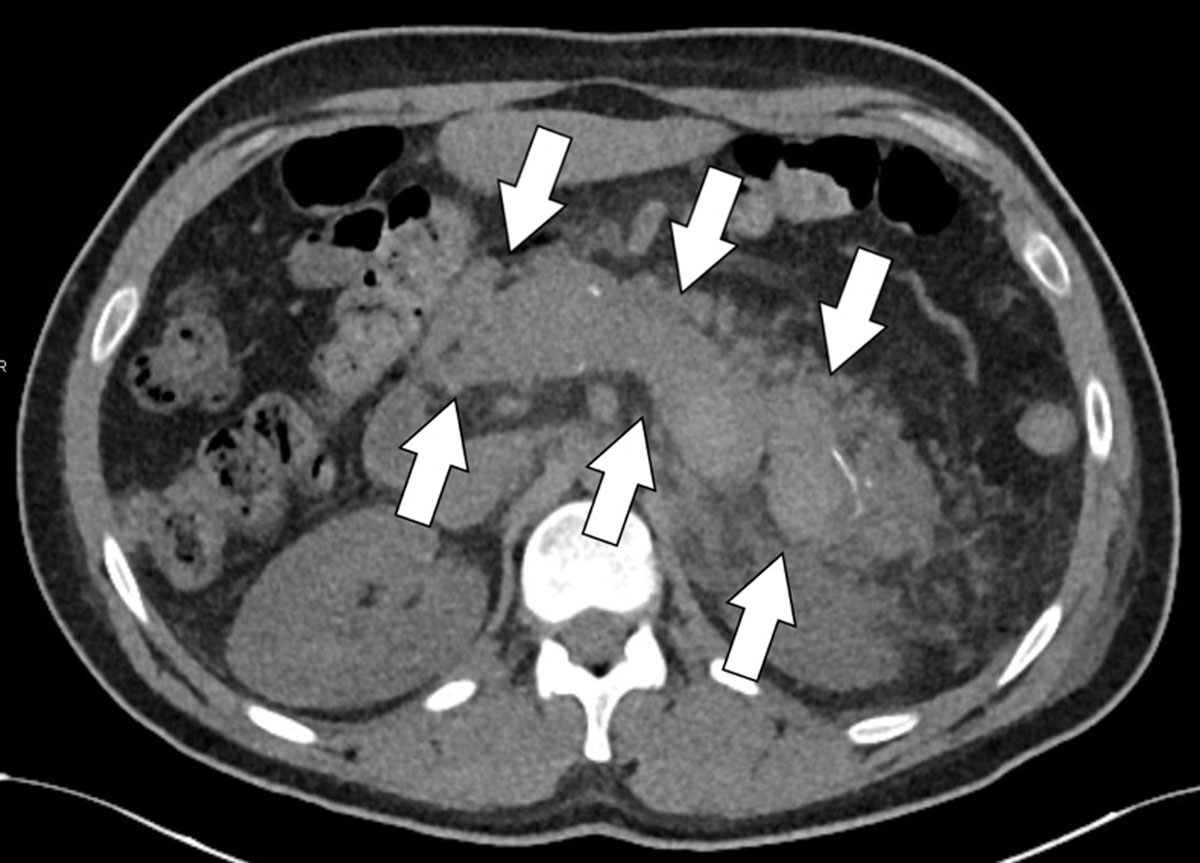

Figure 1a

Axial unenhanced CT-slice revealing a spontaneously hyperdense splenic vein thrombus.

Figure 1b and c

Axial contrast-enhanced portal phase CT slices at the level of the splenic vein (Figure 1b) and portal vein (Figure c) confirming a thrombosis of the splenic vein, extending into the portal vein as well as the part of the intrahepatic segment of the left branch of the portal vein (arrows).